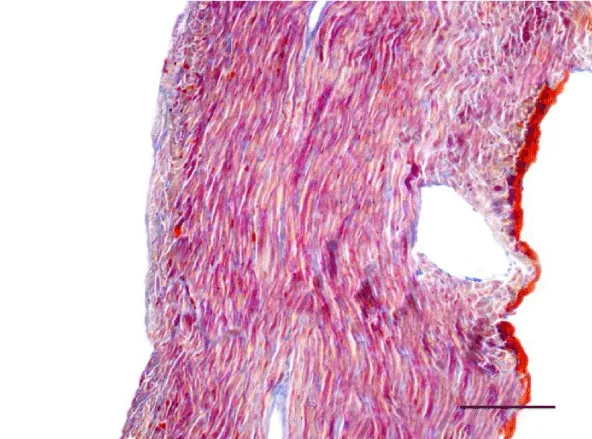

A moderate number of collagen fibers, predominantly in the perivascular zone, as well as the interstitial space, were reported on Mallory’s stain in the wall of the left ventricle in the group of adult (six-month-old) rats. We observed intensively blue-stained, fairly long collagen fibers in the interstitial space which formed complex anastomoses (Figure 17). In senescent (twelve-month-old) rats, collagen fibers in the wall of the left ventricle were abundant both in the perivascular zone and the interstitial space and their alignment was not strictly organized. They had a complex spiral shape and course and were much thicker. Connective tissue in the perimysium was more pronounced (Figure 18). Changes observed in the wall of the right ventricle of six- and twelve-month-old Wistar rats were identical to those described in the left ventricle, however they were characterized as moderate and less expressed. Collagen fibers were shorter and thinner. The perivascular connective tissue was less abundant and the extension of collagen fibers from the perivascular zone towards the interstitial space was less pronounced (Figures 19,20).